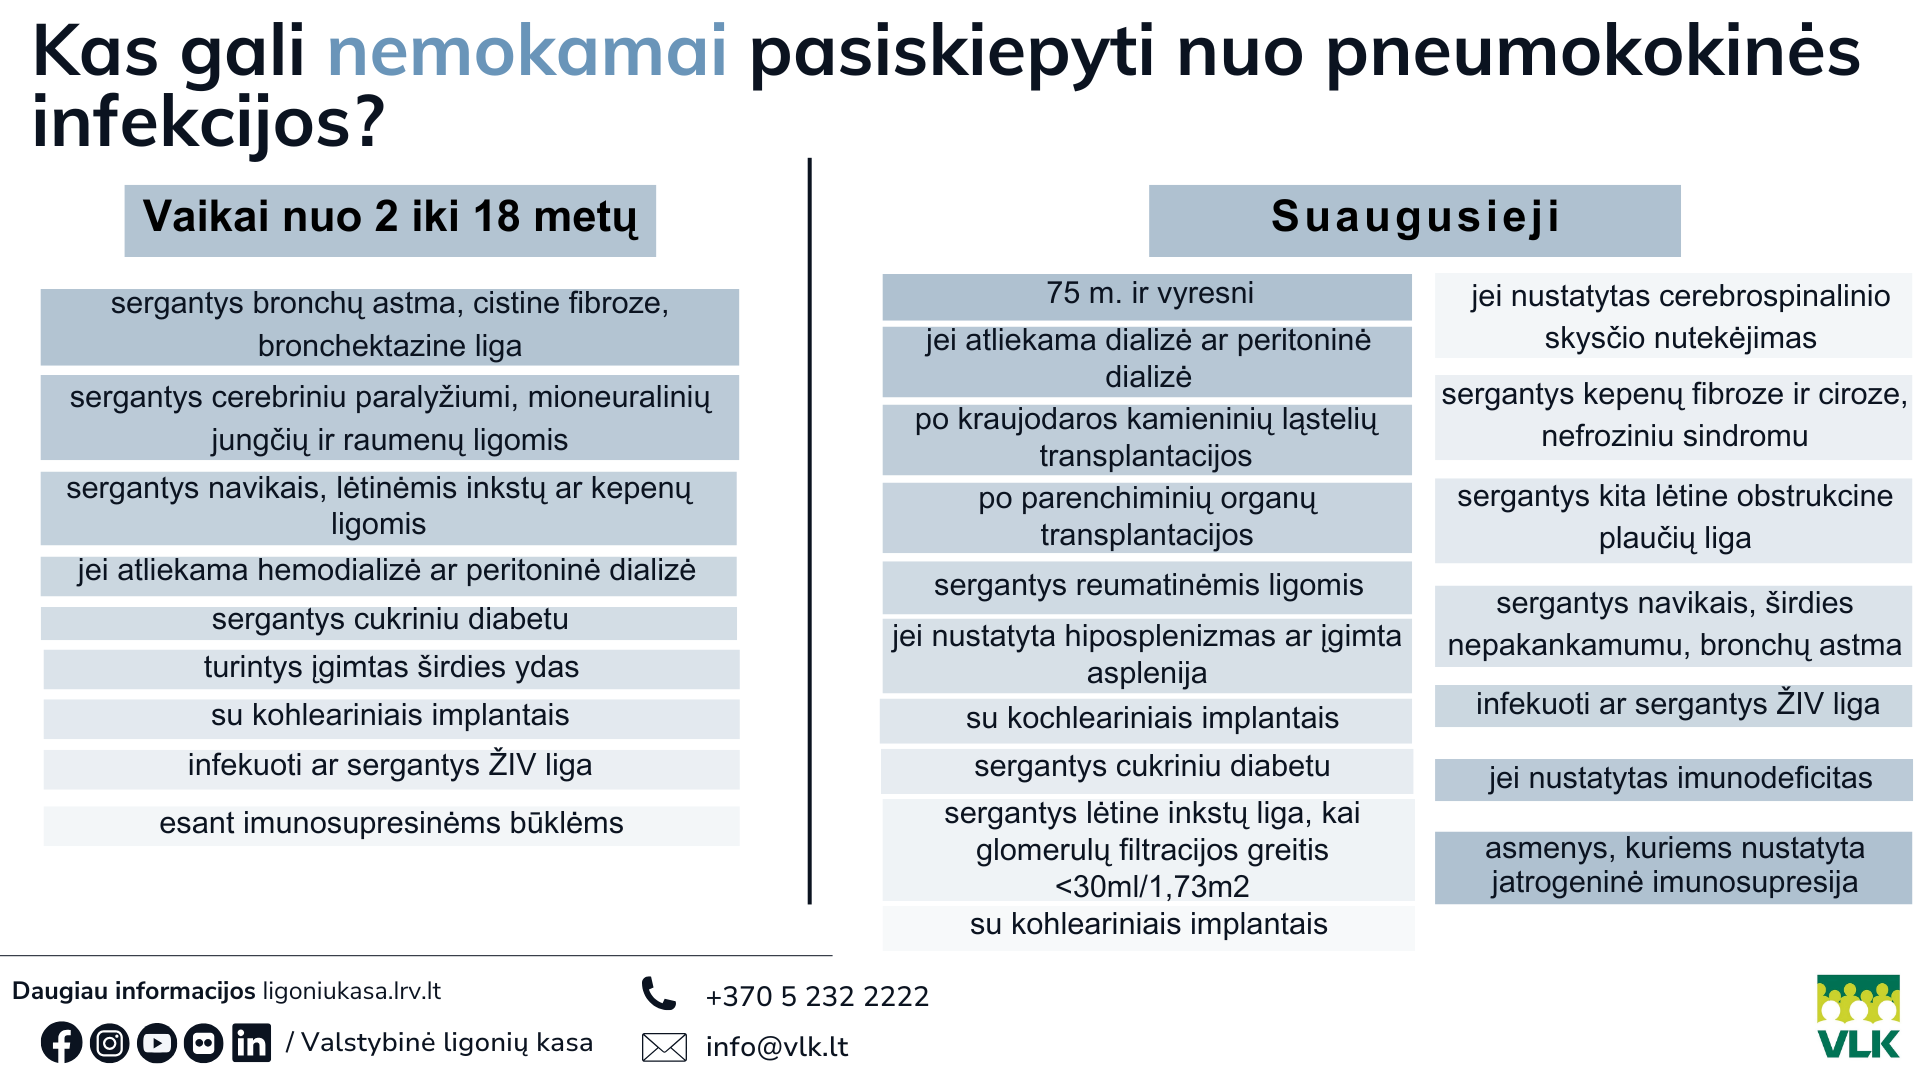

Valstybinės ligonių kasos (VLK) Centralizuotai apmokamų vaistų skyriaus patarėja Agnė Grušeckienė primena, kad nuo pneumokokinės infekcijos Privalomojo sveikatos draudimo fondo lėšomis skiepijamos dvi gyventojų grupės.

Pirmiausia – visi vaikai, kurie pagal vaikų profilaktinių skiepijimų kalendorių yra skiepijami nuo pneumokoko 15-valente vakcina ir rizikos grupėms priklausantys gyventojai, skiepijami 20-valente vakcina.

„Vieną kartą gyvenime fondo lėšomis nemokamai skiepijami sunkiomis lėtinėmis ligomis sergantys vaikai nuo 2 metų, suaugusieji, įrašyti į rizikos grupių sąrašą, bei visi 75 metų ir vyresni gyventojai“, – sako A. Grušeckienė.